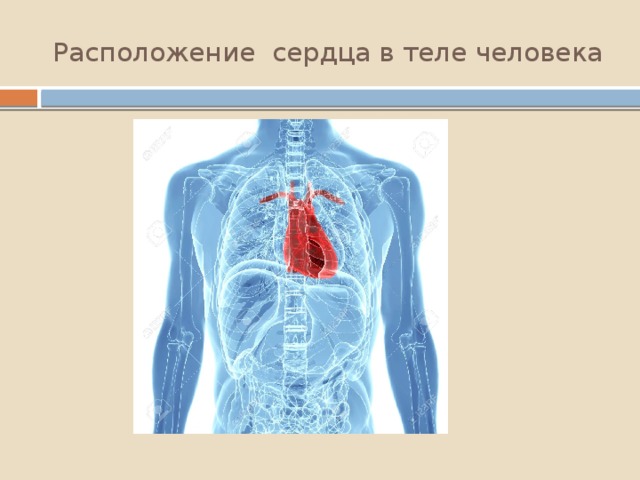

Сердце у человека располагается в грудной полости.

Расположение сердца у человека.

Анатомическое расположение сердца.

Сердце в грудной клетке расположено.

Где расположено сердце у человека анатомия.